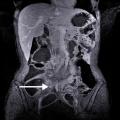

Volvulus du cæcum sur une coupe frontale de tomodensitométrie

ADULTE

OCCLUSION INTESTINALE